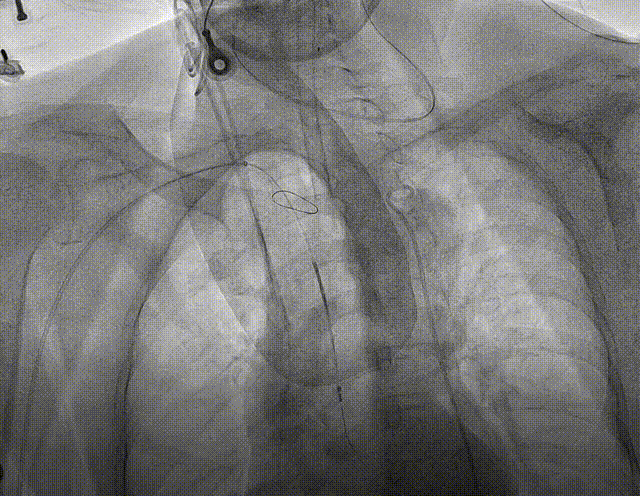

近日,浙江大学医学院附属第二医院王建安教授团队应用MuguetA™球扩瓣为一例重度嵴钙化、极度锐角弓合并68°横位心的患者成功实施TAVR手术,同时采用脑保护装置Sentinel规避脑卒中发生。

患者:女性,74岁,因“活动后胸闷气急1年”入院,超声心动图提示:主动脉瓣口流速6.42 m/s,平均跨瓣压差100mmHg,LVEF66.6%,主动脉瓣钙化并重度狭窄,升主动脉狭窄后扩张,主动脉弓部增宽,二尖瓣中等量反流。

TYPE1型二叶瓣,瓣环面积:359.1mm²,直径:21.7mm;LVOT面积:364.1mm²,直径:22mm;瓣上限制区(瓣上9.2mm)长径:22.4mm,短径:21.8mm;AscAO:45.8mm;左冠高度:11.8mm;右冠高度:14.9mm;心脏角度:68°。

主动脉弓降部走行成锐角、弓顶部可见少许钙化,横位心68%伴有升主动脉扩张。